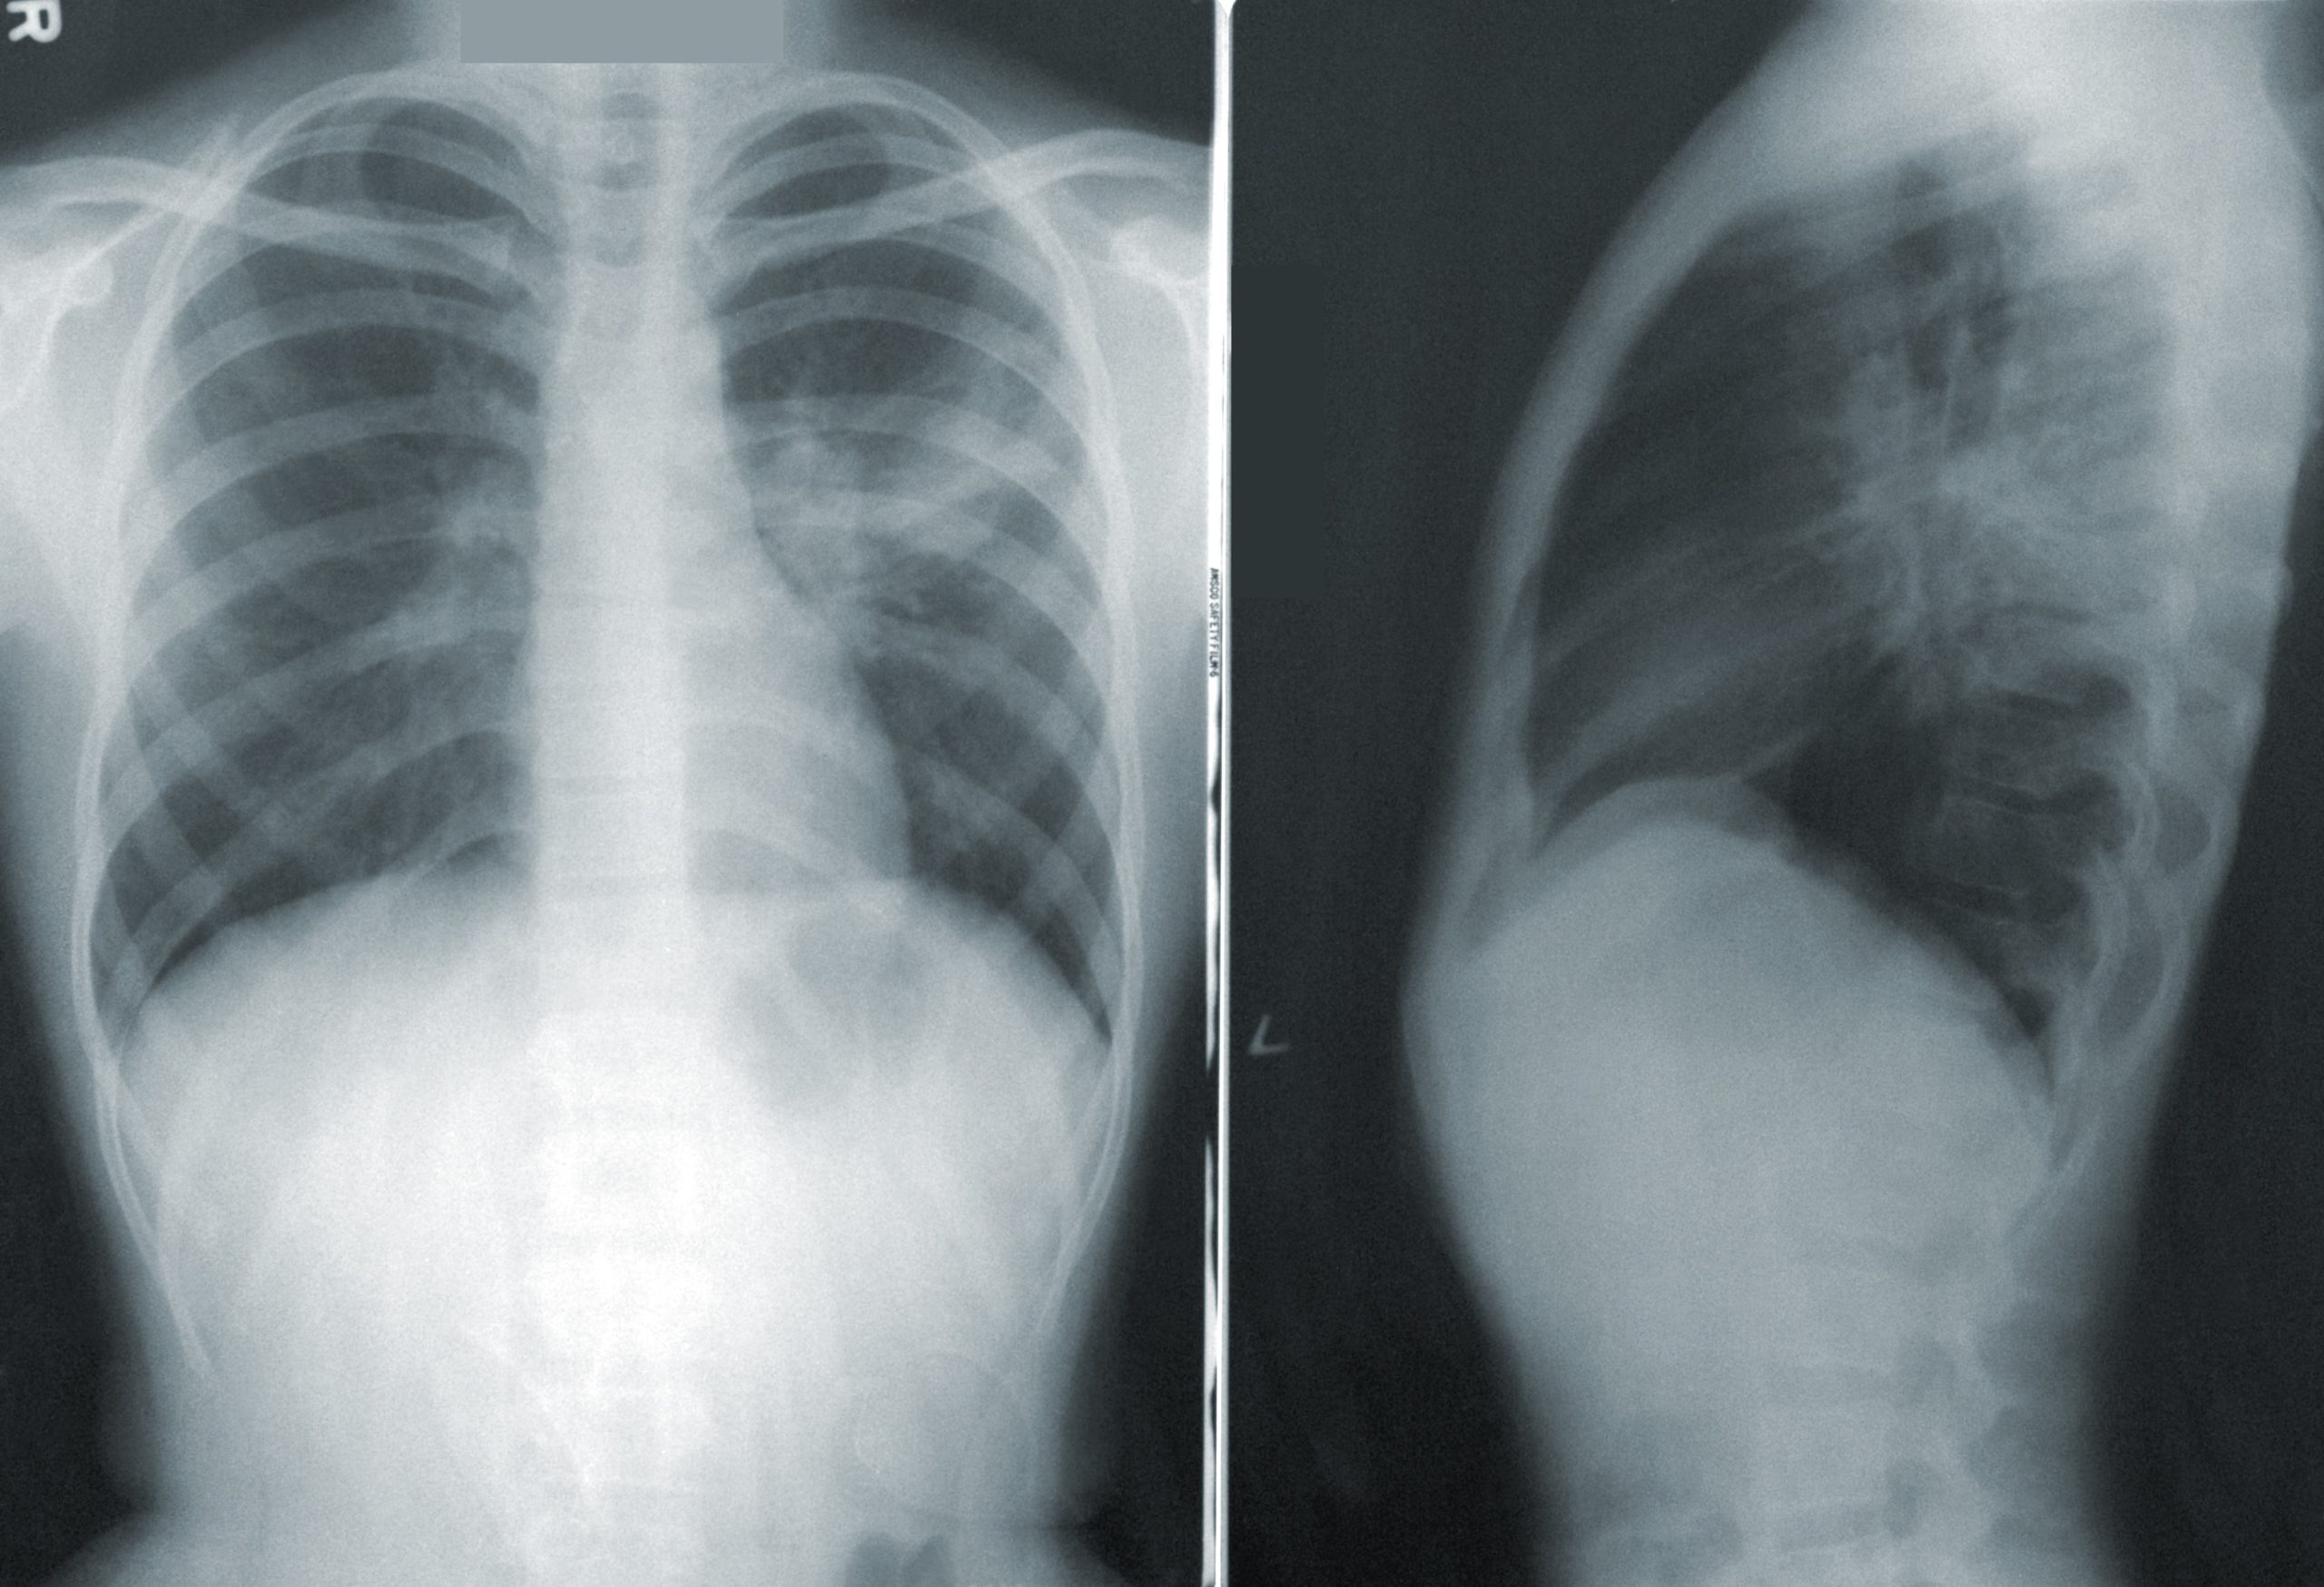

Ο καρκίνος του πνεύμονα εξακολουθεί να αποτελεί κύρια αιτία θανάτων από καρκίνο τόσο σε παγκόσμιο επίπεδο όσο και στην Ταϊβάν. Για την καταπολέμηση του καρκίνου του πνεύμονα και τη βελτίωση των ποσοστών επιβίωσης, η Ταϊβάν δημιούργησε το Εθνικό Πρόγραμμα Έγκαιρης Ανίχνευσης του Καρκίνου του Πνεύμονα, που αποσκοπεί στην έγκαιρη ανίχνευση της ασθένειας, μέσω της διαγνωστικής εξέτασης με αξονική τομογραφία χαμηλής δόσης (LDCT).

Η έγκαιρη ανίχνευση είναι ζωτικής σημασίας για τη βελτίωση των αποτελεσμάτων του καρκίνου του πνεύμονα και ο έλεγχος αυτός έχει αποδειχθεί αποτελεσματικός στη μείωση των ποσοστών θνησιμότητας. Ωστόσο, τα υφιστάμενα κριτήρια ελέγχου στις ΗΠΑ και άλλες χώρες περιορίζουν την επιλεξιμότητα μόνο στους βαρείς καπνιστές, αφήνοντας μια σημαντική μερίδα του πληθυσμού σε κίνδυνο.

Σύμφωνα με το ΑΠΕ-ΜΠΕ, το εθνικό πρόγραμμα προσυμπτωματικού ελέγχου της Ταϊβάν, που εγκαινιάστηκε τον Ιούλιο του 2022, αναγνωρίζεται ότι το οικογενειακό ιστορικό καρκίνου του πνεύμονα αποτελεί σημαντικό παράγοντα κινδύνου οπότε τίθενται στο επίκεντρο δύο κατηγορίες πληθυσμού: τα άτομα ηλικίας 50-74 ετών με ιστορικό βαρέως καπνίσματος, που είναι πρόθυμα να διακόψουν το κάπνισμα ή το έχουν διακόψει τα τελευταία 15 χρόνια, καθώς και τα άτομα (50-74 ετών οι άνδρες και 45-74 ετών οι γυναίκες) με οικογενειακό ιστορικό καρκίνου του πνεύμονα.

Τα προκαταρκτικά αποτελέσματα από τον ένα χρόνο λειτουργίας του προγράμματος ήταν ελπιδοφόρα. Συνολικά εξετάστηκαν σχεδόν 50.000 άτομα, από τα οποία τα 4.406 έλαβαν θετικό αποτέλεσμα ελέγχου και τα 531 διαγνώστηκαν τελικά με καρκίνο του πνεύμονα. Αξιοσημείωτο είναι το γεγονός ότι το 85% των περιπτώσεων καρκίνου του πνεύμονα διαγνώστηκε σε πρώιμο στάδιο (στάδιο μηδέν ή ένα).